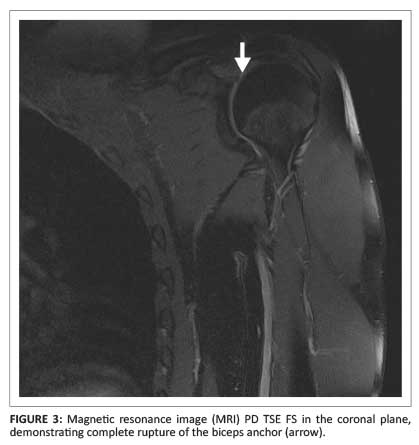

An empty bicipital groove with an intact transverse ligament on the axial plane was diagnostic of a ruptured long head of the biceps tendon (Figure 1). The distal position of the retracted tendon was demonstrated in the sagittal plane (Figure 2). The biceps anchor was demonstrated in the coronal plane (Figure 3).